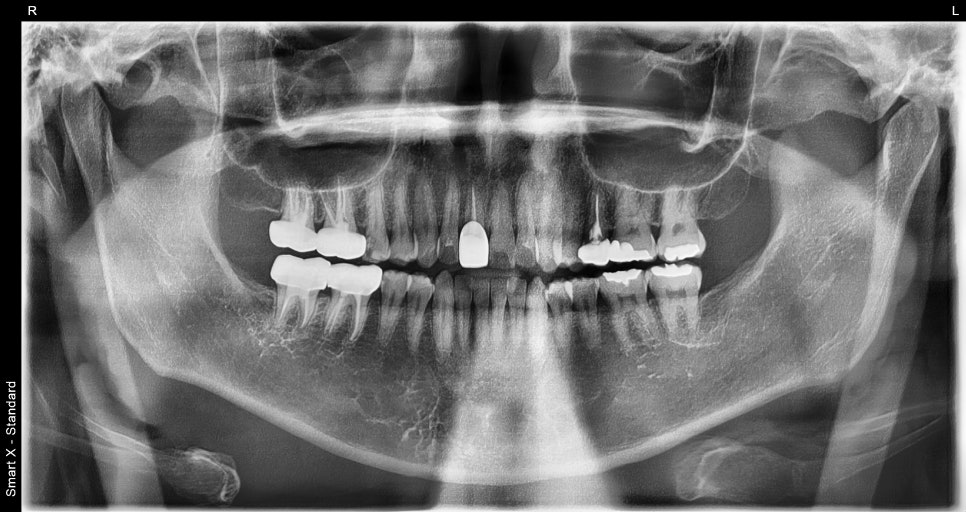

At the dental clinic, the first thing we check

is whether the root of the tooth is okay

At the initial visit

The right tooth broke, and it feels sensitive and painful.

After checking the X-ray, we found that the cavity was so severe that the tooth

had come in broken.

When a molar breaks like this,

root canal treatment is necessary.

<Before treatment / After treatment>